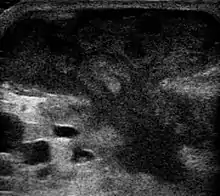

Ultrasound image showing an abscess, appearing as a mushroom-shaped dark (hypoechoic) area within the fibroglandular tissue of the breast.

An abscess is a localized collection of pus (purulent inflammatory tissue) caused by suppuration buried in a tissue, an organ, or a confined space, lined by the pyogenic membrane.[25] Ultrasound imaging can help in a diagnosis.[26]